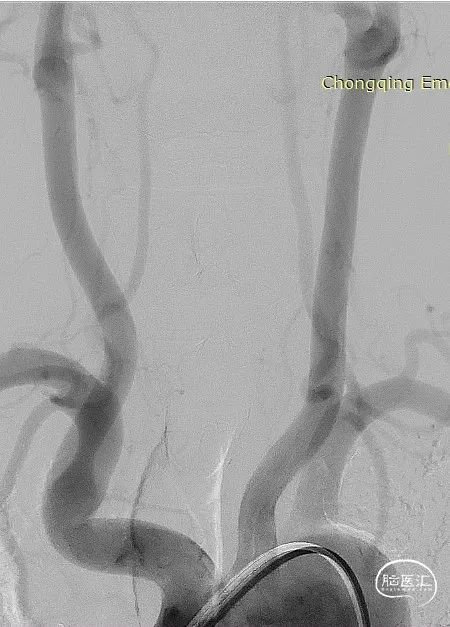

术前影像DSA、DSA 3D

该病例为左侧大脑后动脉P2段微小宽颈动脉瘤,动脉瘤体直径仅0.9mm,载瘤动脉近端血管直径约1.7mm,远端血管直径约1.1mm,且双侧椎动脉均扭曲明显,但左侧后交通动脉粗大,考虑通过左侧后交通动脉为治疗路径,路途遥远,后交通的成角使得微导丝、微导管的操控存在一定难度;由于动脉瘤体小,因此微导管顺利进入动脉瘤腔内并保证安全是手术的关健点;支架微导管系统成功超选进入P3段远端也是手术成功的关键,对于支架的输送性和贴壁性要求极高。

Neuroform Atlas支架全尺寸仅需要通过0.0165或0.017英寸的微导管输送即可,通过性佳,并且其独有的杂合环设计,具备很好的贴壁性能,因此,我们辅助支架选取了3.0mm*15mm Atlas支架。